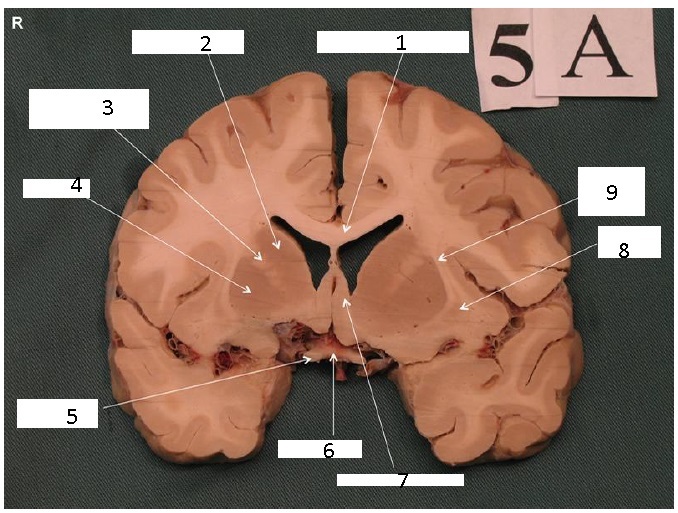

Identify 1

Body of Corpus Callosum

Identify 2

Head of Caudate Nucleus

Identify 3

Anterior Limb of the Internal Capsule

Identify 4

Putamen

Identify 5

Claustrum

Identify 6

Insula

Identify 7

Nucleus Accumbens

Identify 8

External Capsule

Identify 9

Cingulum